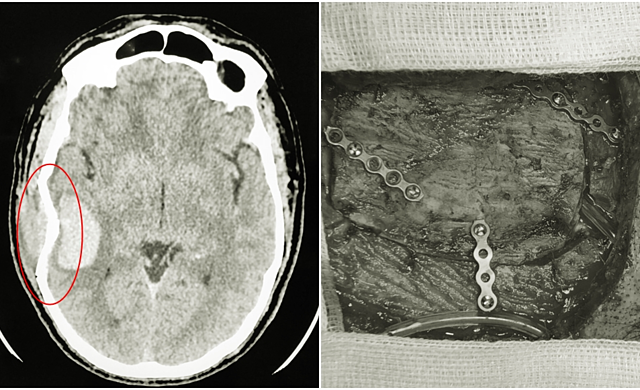

Va chạm mạnh khi đá bóng, cầu thủ bị vỡ xương sọ

Một nam giới 40 tuổi ở Quảng Ninh bị va chạm khi chơi bóng đá gây chấn thương sọ não, vỡ xương sọ,  trong tình trạng nguy kịch.